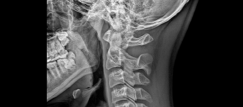

목디스크는 디스크라는 뼈와 뼈 사이의 공간에 위치한 수핵이 나와 경추 신경을 압박하여 발생하는 질환입니다. 목디스크는 인체의 다른 부위에 비해 가장 많이 발생하는 질환이며, 나이가 들면서 더욱 빈번하게 발생하게 됩니다. 이번 글에서는 목디스크의 증상 3가지를 알아보겠습니다.

목디스크 환자들은 근육 약화 증상을 경험할 수 있습니다. 이는 경추신경이 압박되어 신경이 손상을 입어 발생합니다. 근육 약화는 일상생활에서 물건을 들거나, 무거운 것을 옮기거나, 자세를 유지하는 것조차도 어렵게 만들어질 수 있습니다.

경추신경이 압박되면 신경의 전기 신호가 잘 전달되지 않아 저림 현상이 발생할 수 있습니다. 이는 손가락이나 팔, 어깨, 목 등 신체의 다른 부위에서도 느껴질 수 있습니다. 또한, 신경의 손상이 심한 경우, 팔과 다리를 움직이는 것이 어렵게 될 수 있습니다.